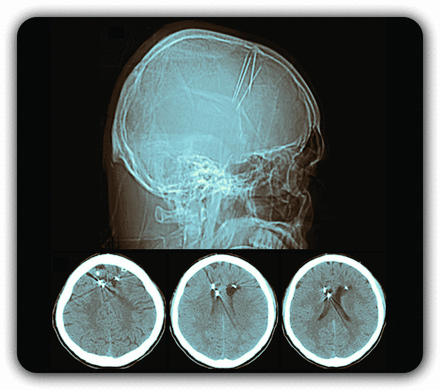

封面图片:CT扫描显示多个针头从冠状缝投射到大脑,由传统的治疗师试图治疗癫痫发作。彩色的辛迪Abair,神经病学高级图形编辑器。首页看到页面1064年。